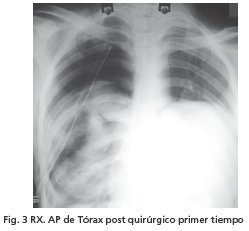

Llegando al diagnóstico de quiste hidatídico gigante bilateral. Se realizó tratamiento quirúrgico en 2 tiempos por el gran compromiso pulmonar. En fecha tres de agosto de 2006 se realizó toracotomía derecha y quistectomía con cierre de fístulas broncopleurales, hallando quiste de 20 cm. de diámetro que en el intento de su extracción se desgarra la membrana quistica. Placa Rx control (Fig 3)